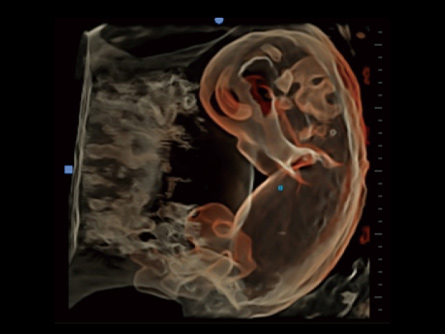

CHISON lleva la Salud de la Mujer a nuevos niveles con máquinas de ultrasonido dedicadas. Diseñadas para ginecólogos y obstetras, nuestros sistemas ofrecen una claridad sin igual en la imagen, respaldando diagnósticos seguros. Desde la atención prenatal hasta los exámenes ginecológicos, las soluciones de ultrasonido de Salud de la Mujer de CHISON proporcionan una calidad de imagen superior, mejorando la comprensión de anatomías complejas. Eleve la atención al paciente con nuestra tecnología fácil de usar y eficiente.